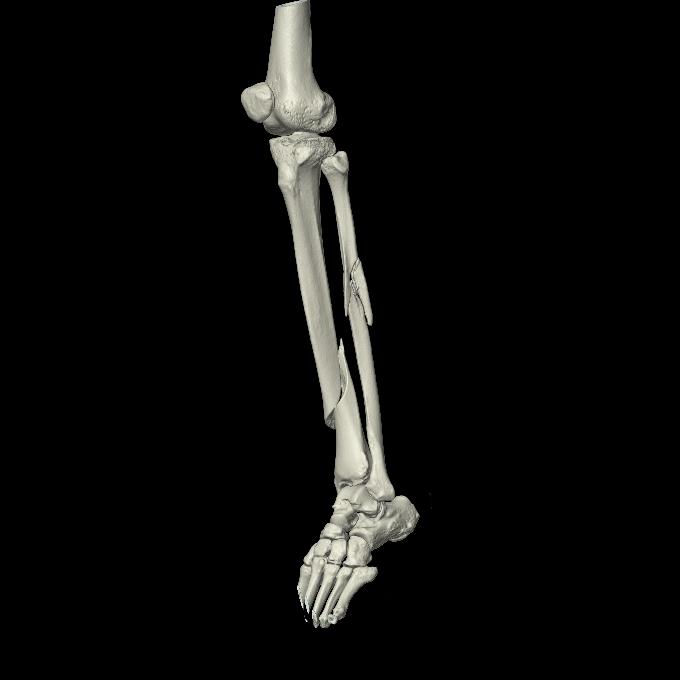

102803 1/12(キウスなし) 1/27 左下腿 4R 30歳女性 左脛骨軸内釘

102755 1/4 2R 1/15 2R 右足関節 68歳女性 右三果脱臼骨折

103177 3/11 右足 2R 3/16 右足 2R リスフラン脱臼 55歳男性